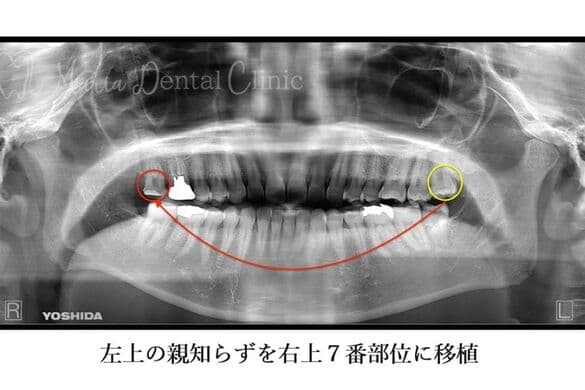

症例紹介

右上の奥歯が歯根破折を起こし、抜歯が避けられない状態となった患者様の症例です。

患者様はインプラント治療に抵抗をお持ちでしたが、幸い左上に健康な親知らずが残っていたため、その歯を移植する「歯牙移植」により欠損部を補いました。

口腔外科医と歯内療法専門医が連携し、術後の根管治療・経過観察を経て良好な結果が得られた症例です。

| 治療内容 | 歯牙移植 |

|---|---|

| 治療期間 | 3ヶ月 |

| 治療回数 | 3回 |

| 治療費用 | 110,000円(税込)※精密根管治療(大臼歯)は含みません ※処置当時の料金です |